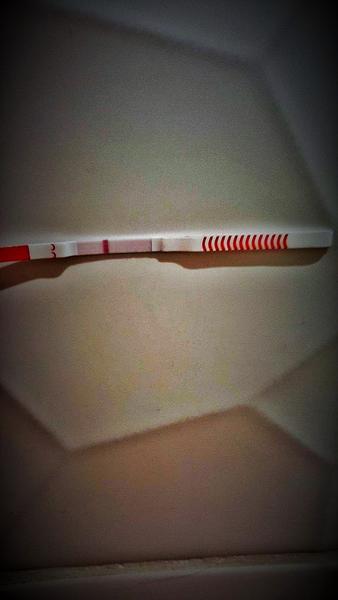

@zuzana92521 na Tvojom vcerajsom teste vidim slabuckeho dusika - neviem, ci aj Ty to na tejto fotke vidis - nalavo od kontrolnej (je to Pepino, ci?)...Neviem, ci je tam naozaj, alebo mam len vidiny - velmi zlu foto si dala, je dost rozmazana, ak mozes, odfot este raz...Jednoznacne testuj za 2-3 dni...Drzim palceky, nech sa Tvoje pocity nemylia a najdes si // - ako po nich tuzis 😉...Hod zas potom foto, ak by si testovala 🙂